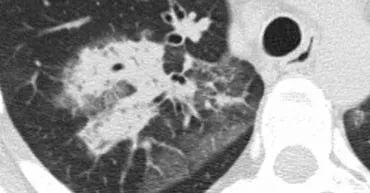

下图,我们看到实变和GGO持续存在和体重减轻,没有感染的迹象。

这表明这是一种慢性疾病。

没有蜂窝状或牵张性支气管扩张,所以我们可以排除纤维化。

体重减轻暗示着一种恶性疾病。

组织学检查显示支气管肺泡细胞癌。